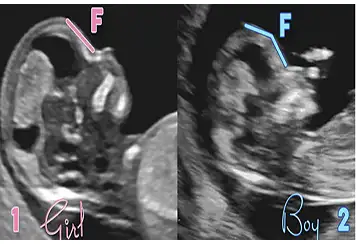

Bebeğimin cinsiyeti